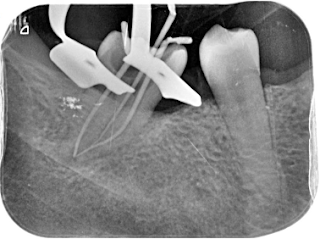

Seguimos permeabilizando los conductos y midiendo la longitud de trabajo: MV: 20 mm ; ML: 21 mm ; D: 17 mm. Se instrumenta hasta calibre apical 25/04, irrigando durante toda la instrumentación con hipoclorito al 4,25% y pasando la lima del 10 entre limas rotatorias.

Acabo de la instrumentación se realiza la irrigación final con hipoclorito 4,25%- EDTA 17% - Hipoclorito 4,25%, con activación sonica. Se secan los conductos con puntas de papel medidas y se obtura con la técnica de ola continua de calor con conos de guttapercha de 4% calibradas a 25 para los conductos mesiales y 30 para el distal. Como reconstrucción provisional se coloca algodón y cavit.